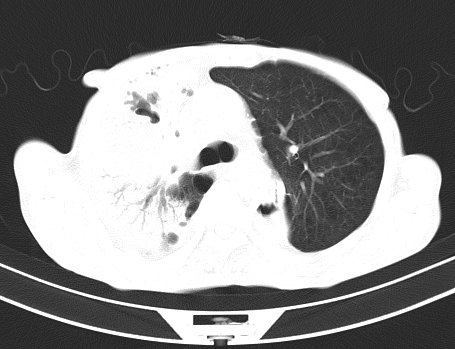

以下是引用gaoshengjiang在2008-5-30 19:53:00的发言:[br]右上叶可见大片实变影,其内可见充气支气管影及囊状影,右上叶尖端支气管走形区可见结节样影,左侧胸腔内可见胸腔胃影。纵隔淋巴结肿大。[br]考虑:1.右上肺阻塞性肺炎伴肺脓肿形成。支持转移所致。[br] 2.左侧胸腔胃。